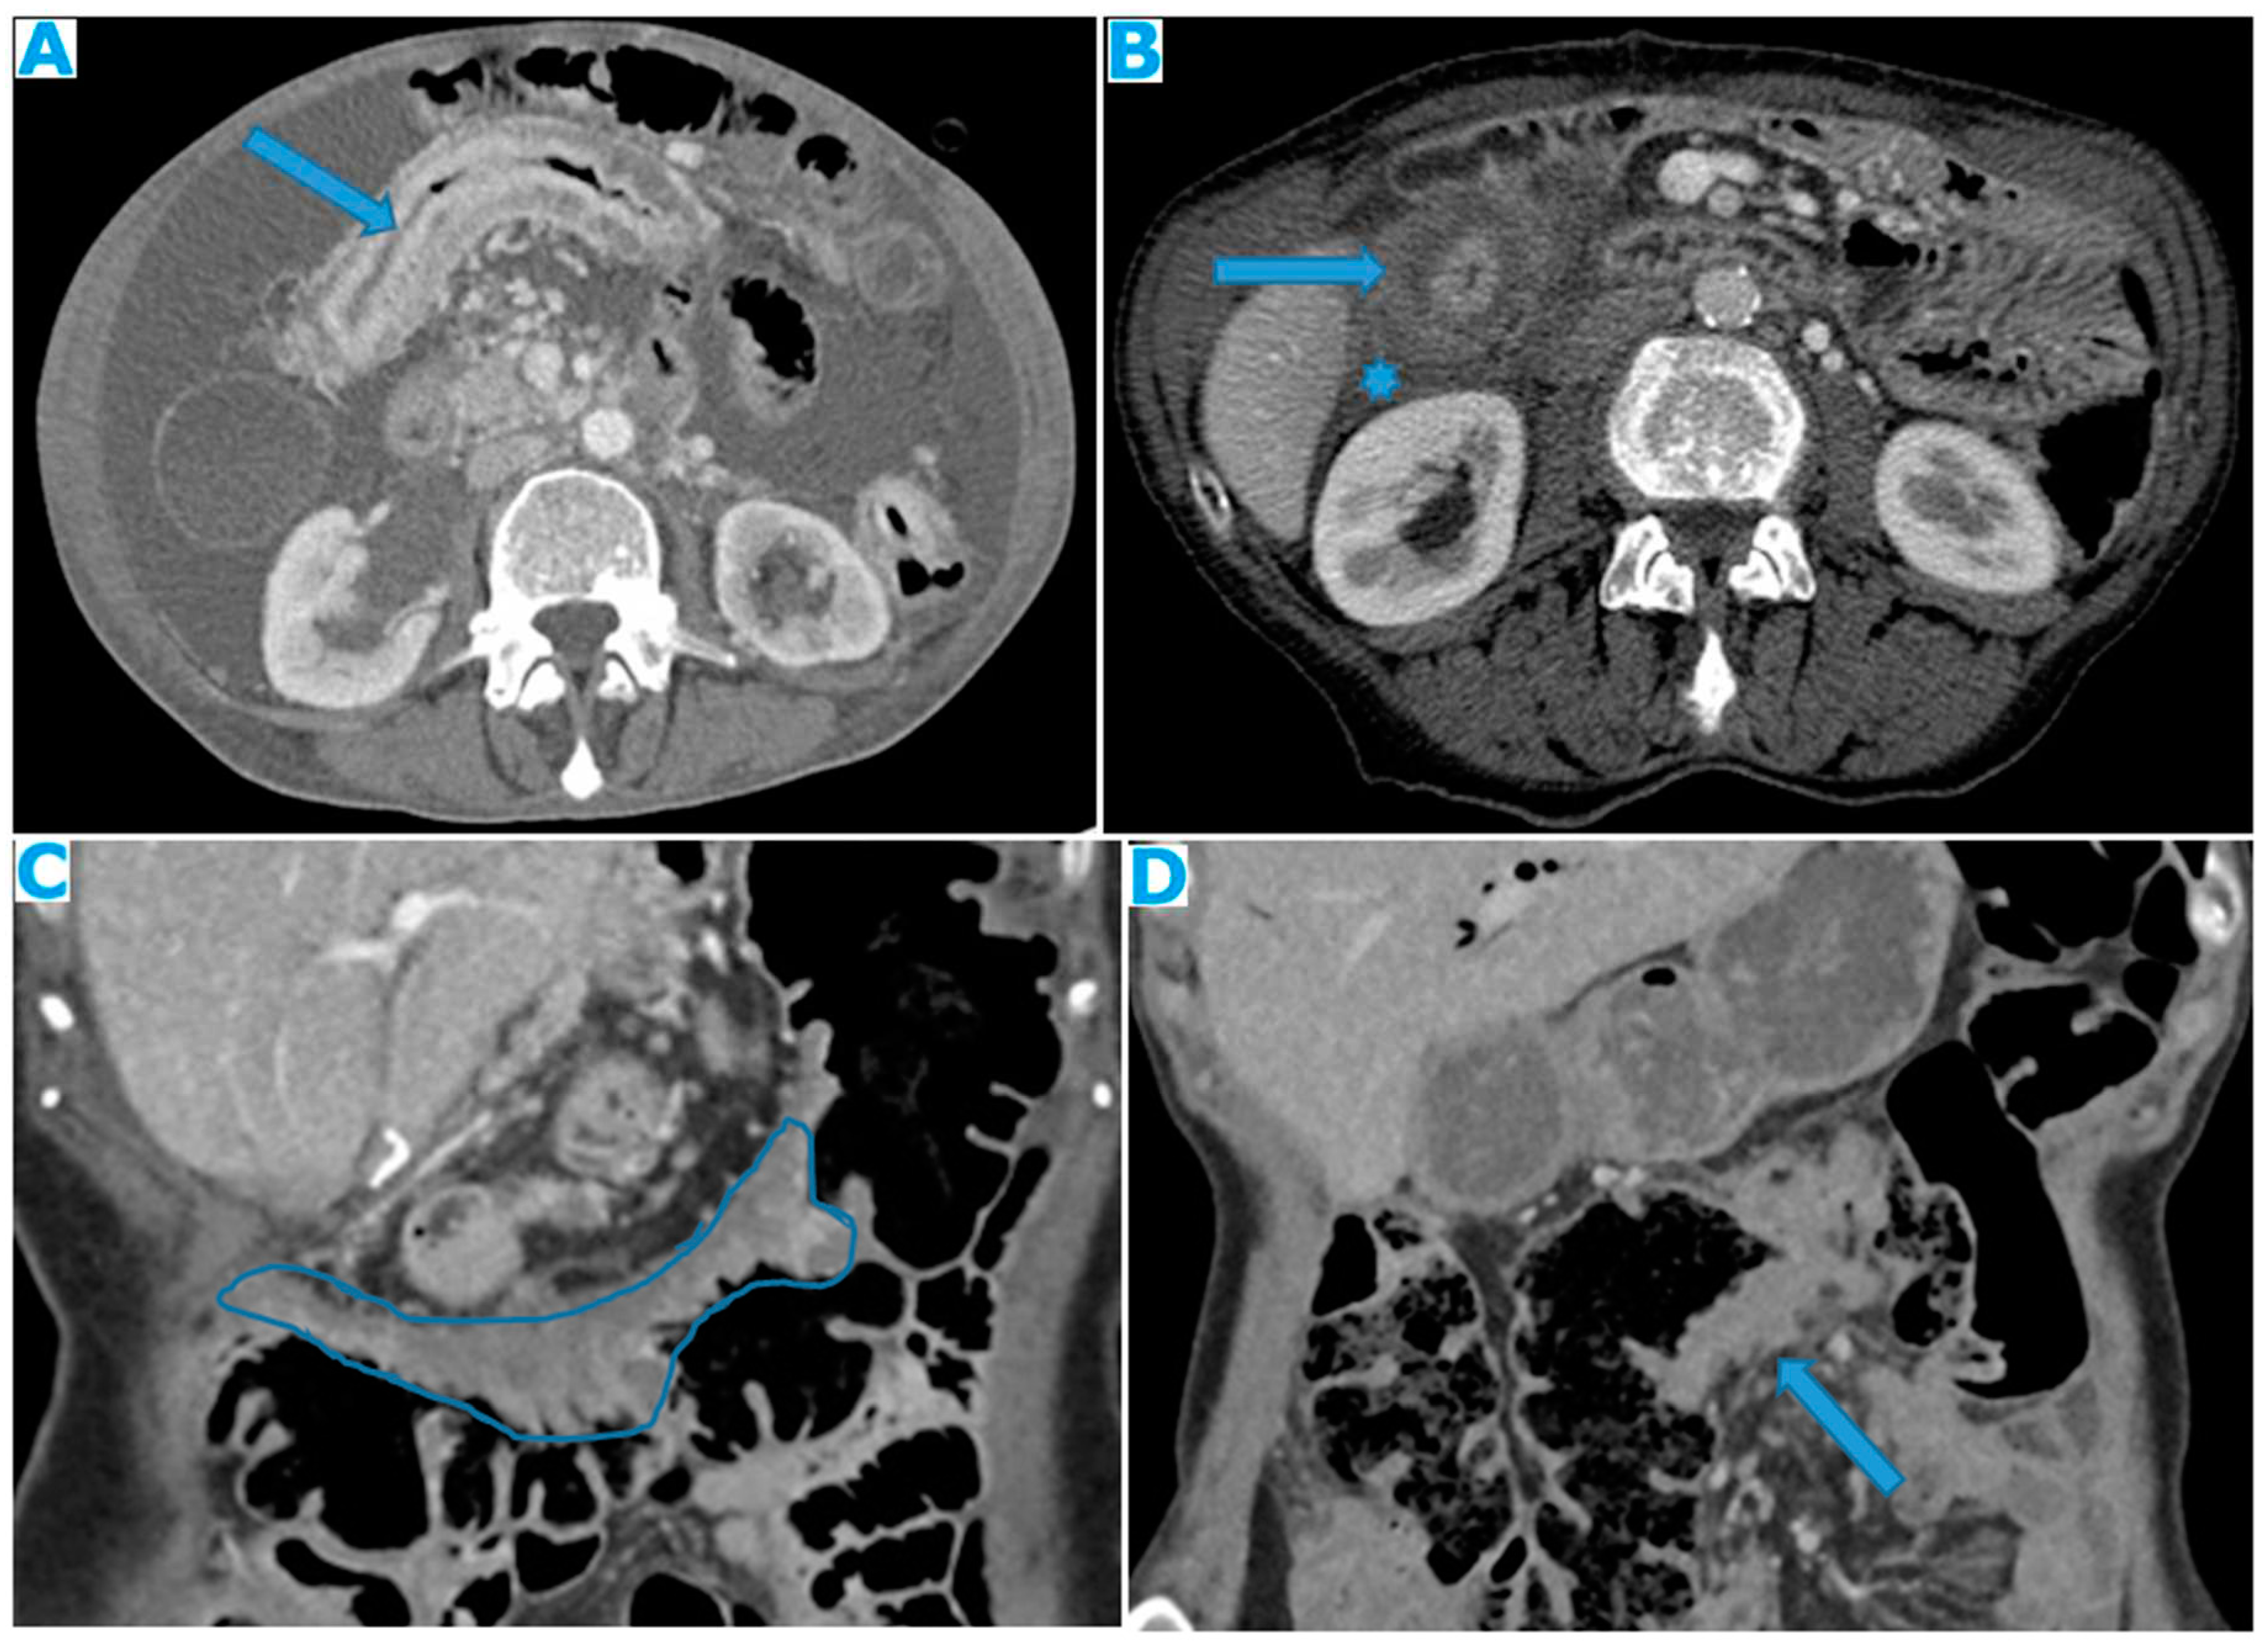

Figure 24.

Axial CE-CT (A), axial T2WI (B), axial CE portal phase FS T1WI (C). PC from endometrial carcinoma: Deposit seeding within the mesenteric leaves.